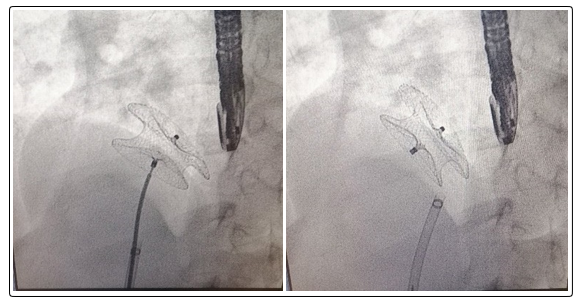

A device with a waist diameter similar to or in large defect up to 2 mm bigger than the stretched ASD diameter was chosen. The position and stability of device was assessed by fluoroscopy and transesophageal echocardiography (Figure 1). Care was taken to ensure that the device did not obstruct the right pulmonary veins, caval veins, coronary sinus or the mitral valve. Any residual shunt was evaluated by color Doppler echocardiography on TEE. The device was then released from the delivery system and final assessment of the position of the device was performed by TEE.

Figure 1